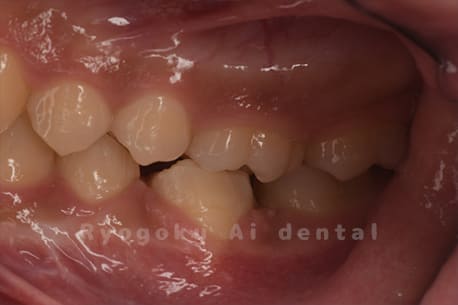

他院で虫歯が大きいため、また、根っこが病気になっているため、親知らずとともに抜歯し、2本インプラントを進めらた患者様です。親知らず(8番)と共に7番目の歯を保存不可能と判断し、2本抜歯を行い、反対側の親知らずのみを1本分移植しました。当初は親知らずの部分までもインプラントを提案されていましたが、噛み合わせの関係上、特に必要ないことを納得していただき、7番目の歯のみに移植治療を行なった患者さんです。